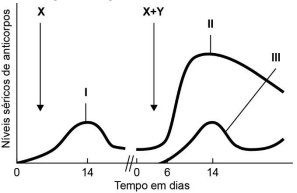

Em um experimento, um mamífero recebeu inicialmente um

inóculo contendo a substância X. Após algumas semanas, o animal

recebeu um segundo inóculo, contendo agora uma mistura das

substâncias X e Y. A quantidade de anticorpos no sangue dessa

cobaia foi medida ao longo de todo o experimento e está

registrada no gráfico a seguir.

A análise do gráfico permite concluir que

A análise do gráfico permite concluir que